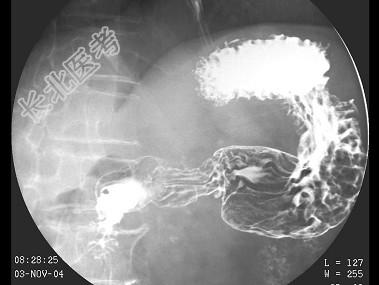

- 单项选择题男,78岁, 上腹痛1月余,返酸, 无嗳气,空腹加重。体检: 上腹压痛,结合图像, 最可能的诊断为 ( )

C、胃癌

D、十二指肠憩室

E、十二指肠占位